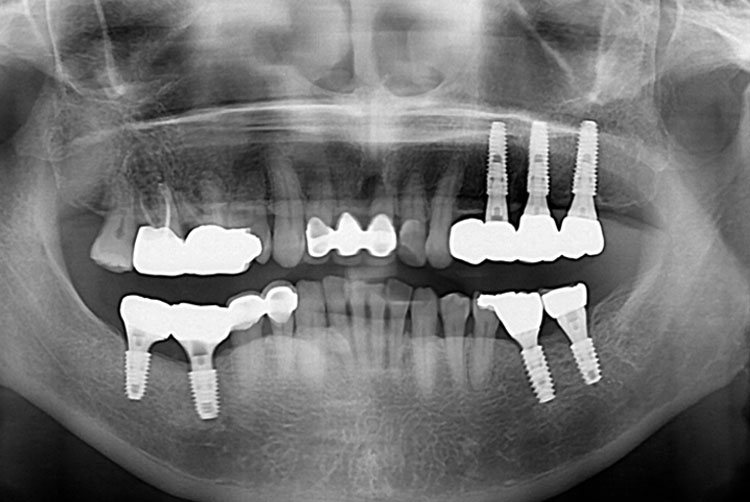

유정림_후.jpg

치료후 : 2019-08-08

세종치과는 많은 환자와 다양한 케이스를 바탕으로 항상 편안한 임플란트 수술을 제공하고자 노력하고,

오래동안 튼튼히 쓸 수 있는 임플란트 수술을 가장 큰 목표로 삼고 있습니다.